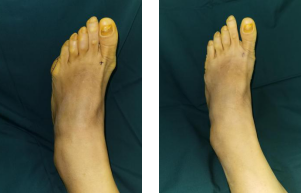

第二天,石荣剑院长、徐明亮主任、魏笛医生手术团队为吴女士进行了左足拇外翻、小趾内翻截骨矫形固定、韧带松解、关节囊缝合术。

术后第2天,吴女士顺利出院。

术前设计(左图) 术后即刻(右图)